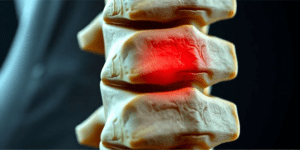

¿Qué es la Ciática? Síntomas, causas y tratamiento

Pinzamiento Lumbar: Soluciones Efectivas para el Dolor Ciático y de Espalda ¿Sufres de dolor en la espalda o en la pierna desde hace meses? ¿El